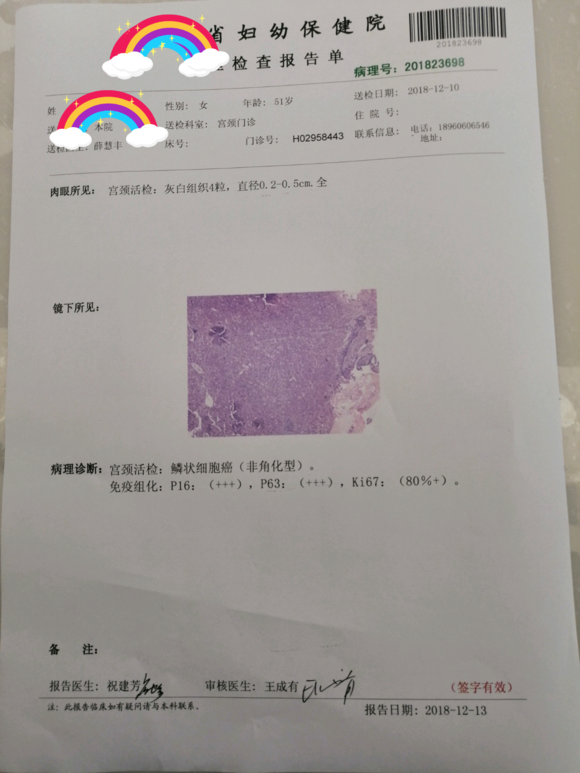

和你的故事 02019-04-09 患者家属我妈妈的病理结果报告,3期c1,大家可以帮忙看看吗,跪求了!我很急,谢谢!想知道是否严重,目前等术后出院后去肿瘤医院...